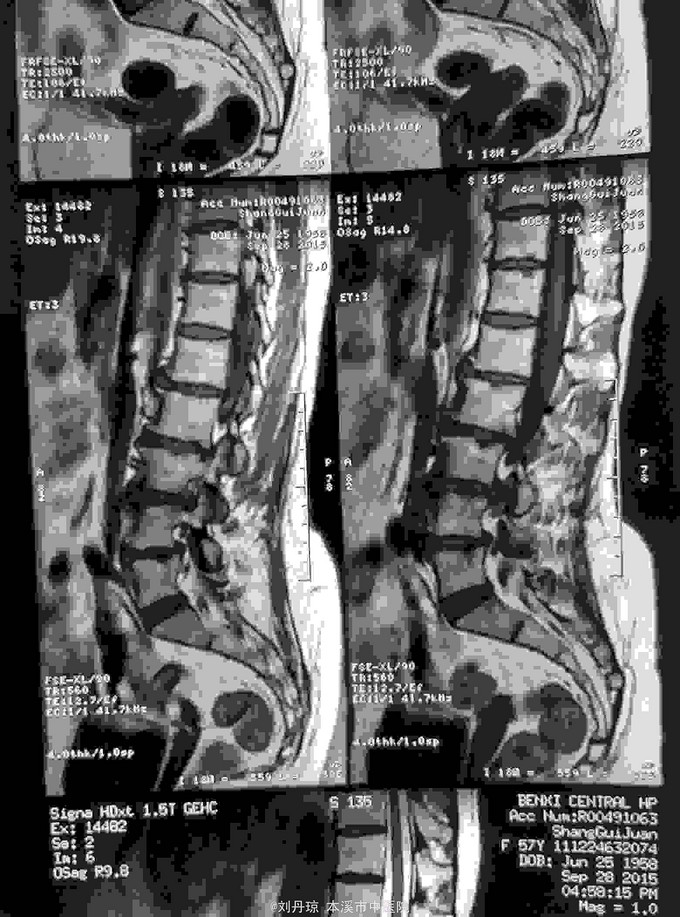

腰部疼痛伴右下肢放射痛麻木感半年,加重2月。患者半年前劳累后感到腰部疼痛伴右下肢放射痛麻木感,近2月病情加重来诊。

查体:L1—S1棘突右旁压痛阳性。直腿抬高实验左70度,右40度。 直腿抬高加强实验左侧阴性,右侧阳性。腰椎功能障碍。 辅查:CT: L1—S1椎间盘突出。

诊断:腰椎间盘突出症 治疗:针灸、雷火灸、中药熏药治疗、小针刀治疗、骶管注射治疗、营养神经药物治疗、脱水药物治疗,当归地黄饮加味。